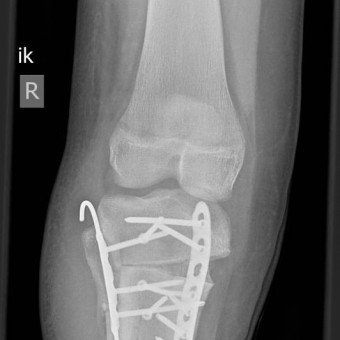

Hilfe für Kinder in Angola

Service Excellence heisst für uns auch, dass wir nicht nur Kindern und Jugendlichen in der Schweiz helfen. Ein Beispiel dafür ist unsere Zusammenarbeit mit dem Friedensdorf International, das durch die grosszügige Unterstützung durch den Hilfsfonds der Schulthess Klinik finanziert wird. Über diese Partnerschaft konnten wir zwei Kinder aus Angola operieren. Beide hatten schwere Fehlstellungen an den Beinen und dadurch kaum Chancen auf eine gute Zukunft in ihrer Heimat.